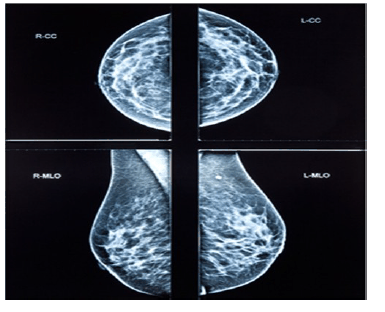

Uma paciente de 32 anos de idade, preocupada pelo fato de sua tia materna ter falecido por um câncer de mama aos 58 anos de idade compareceu à consulta e o médico solicitou uma mamografia digital. A imagem do exame realizado é apresentada a seguir.

O laudo do exame revela mamas densas com ausência de nódulos, apresentando linfonodos no respectivo prolongamento axilar, com pequenos cistos distribuídos em ambas as mamas com até 3 mm de diâmetro em sua dimensão máxima. O radiologista atribuiu a classificação BIRADS escore 2 para ambas as mamas.

Considerando esse caso clínico e os conhecimentos relativos ao rastreamento do câncer de mama, julgue os itens a seguir.

Uma paciente de 32 anos de idade, preocupada pelo fato de sua tia materna ter falecido por um câncer de mama aos 58 anos de idade compareceu à consulta e o médico solicitou uma mamografia digital. A imagem do exame realizado é apresentada a seguir.

O laudo do exame revela mamas densas com ausência de nódulos, apresentando linfonodos no respectivo prolongamento axilar, com pequenos cistos distribuídos em ambas as mamas com até 3 mm de diâmetro em sua dimensão máxima. O radiologista atribuiu a classificação BIRADS escore 2 para ambas as mamas.

Considerando esse caso clínico e os conhecimentos relativos ao rastreamento do câncer de mama, julgue os itens a seguir.

Uma paciente de 32 anos de idade, preocupada pelo fato de sua tia materna ter falecido por um câncer de mama aos 58 anos de idade compareceu à consulta e o médico solicitou uma mamografia digital. A imagem do exame realizado é apresentada a seguir.

O laudo do exame revela mamas densas com ausência de nódulos, apresentando linfonodos no respectivo prolongamento axilar, com pequenos cistos distribuídos em ambas as mamas com até 3 mm de diâmetro em sua dimensão máxima. O radiologista atribuiu a classificação BIRADS escore 2 para ambas as mamas.

Considerando esse caso clínico e os conhecimentos relativos ao rastreamento do câncer de mama, julgue os itens a seguir.

Uma paciente de 32 anos de idade, preocupada pelo fato de sua tia materna ter falecido por um câncer de mama aos 58 anos de idade compareceu à consulta e o médico solicitou uma mamografia digital. A imagem do exame realizado é apresentada a seguir.

O laudo do exame revela mamas densas com ausência de nódulos, apresentando linfonodos no respectivo prolongamento axilar, com pequenos cistos distribuídos em ambas as mamas com até 3 mm de diâmetro em sua dimensão máxima. O radiologista atribuiu a classificação BIRADS escore 2 para ambas as mamas.

Considerando esse caso clínico e os conhecimentos relativos ao rastreamento do câncer de mama, julgue os itens a seguir.